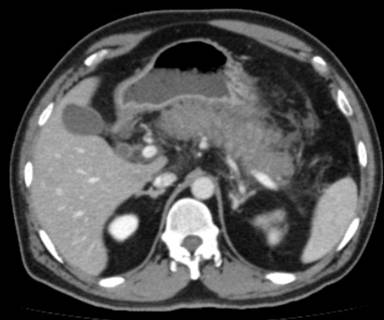

On physical examination, he had a heart rate of 110 beats/min and a respiratory rate of 22 cycles/min. His blood pressure was 124/86 mm of Hg and he was afebrile. Abdominal examination revealed epigastric tenderness with guarding, liver dullness was not obliterated. We made a diagnosis of acute pancreatitis on the basis of clinical, laboratory data and radiologic findings. serum amylase level was 2,215 U/L (reference range: 30-100 IU/L) and CECT abdomen and pelvis showed features of interstitial pancreatitis (Figure 1). On the day of admission his liver function test, serum calcium and serum triglycerides level were normal (Table 1). Chest X-ray showed a small left pleural effusion and ultrasound of the abdomen did not show gallstones. He did not smoke or consume alcohol, and was not obese (body mass index: 27 kg/m2).

Figure 1. CECT abdomen on day 1 showing interstitial pancreatitis with peripancreatic inflammation. |